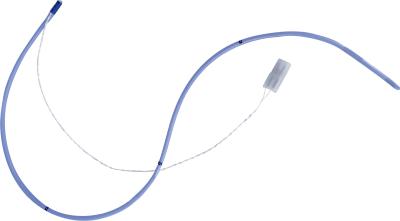

5mW Ntc 5k Thermistor , Low noise iR temperature sensor For intestine

High Light:5k intestine ir temperature sensor, Low Noise ntc 5k thermistor, 5mW ir temperature sensor

5K 10K Medical Temperature Sensor Application Medical Equipment According to application, medical temperature sensor will be grouped into 3 types: body surface temperature sensor, body cavity temperature sensor and disposable body temperature sensor. Body surface temperature sensor is used to measur... View More